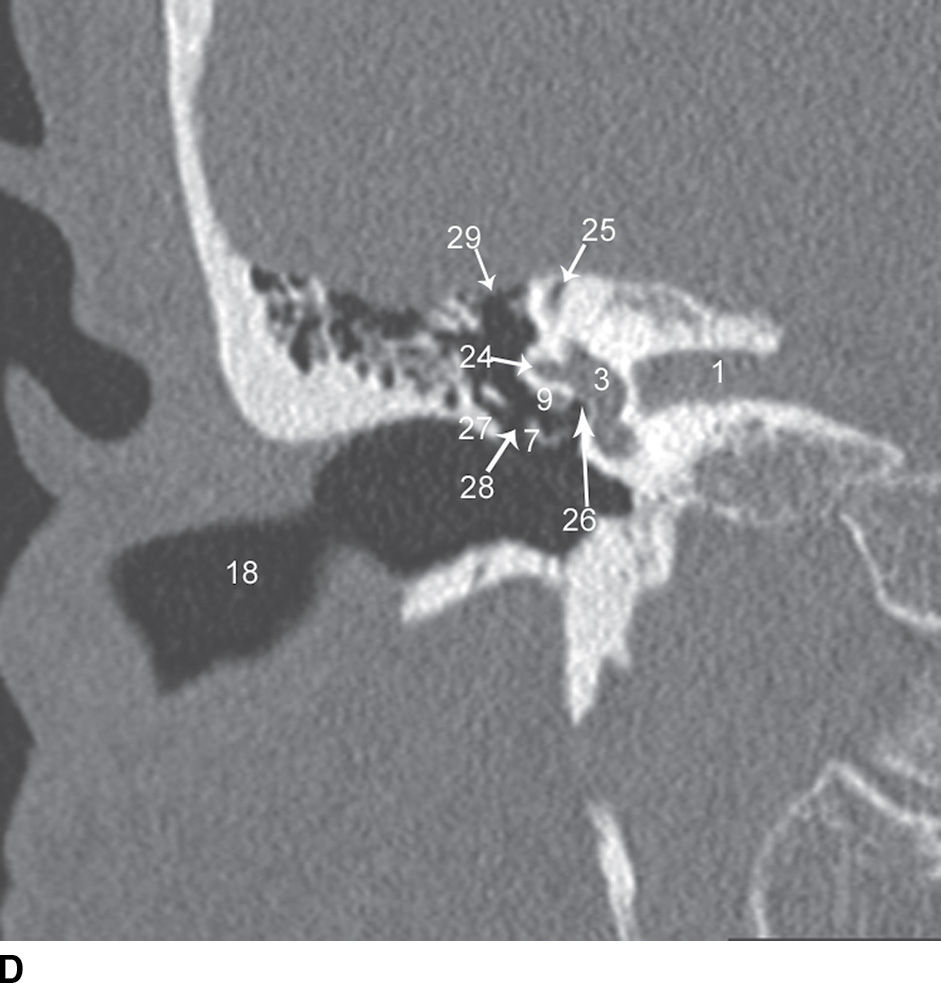

Coronal CT images show the normal anatomy of the temporal bone from

Coronal CT images show the normal anatomy of the temporal bone from Ct Anatomy Of Temporal Bone Some structures are discussed in more detail with emphasis on related. In this review we present the normal axial and coronal anatomy of the temporal bone by scrolling through the images. Several intrinsic channels, intrinsic fissures, and extrinsic sutures are often apparent on ct images and can mimic fractures (pseudofractures) (1). We have created an atlas of the temporal bone,. Ct Anatomy Of Temporal Bone.